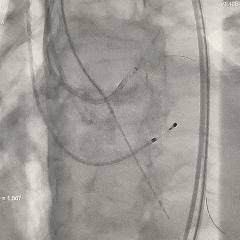

脱钩后造影

无窦侧深度约瓣上2mm,小弯侧深度基本零位,瓣膜植入位置尚可,瓣架形态呈现微倒梯形,可见少量瓣周漏,右冠显影正常

左冠切线位评估

左冠导管造影,可见左冠显影可,考虑导管挤压瓣叶可能,决定将导管拉出冠脉口再次造影评估

左冠再次造影评估

导管拉出左冠口后造影,可见冠脉灌注正常,瓣叶未超过冠脉开口

最终评估

超声测量AVmax=2.1m/s,PGmax=17mmHg,提示少量瓣周漏,间隔侧瓣架深度为真实瓣环零位

考虑球囊后扩的操作会进一步增加冠脉阻挡风险,并存在较高瓣膜上跳风险,综合患者情况可,决定不再进行球囊后扩。